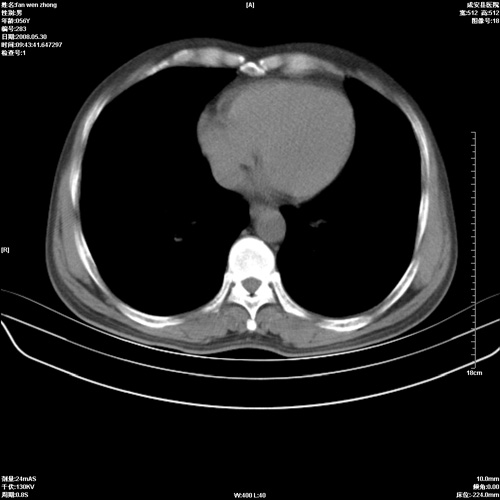

病人 男 56岁 一周前高热,体温达39-40度,经抗炎治疗后,体温渐降,达37,5-38度,轻微咳嗽,胸部不适 查白细胞为1.3万 行ct检查,请分析。

双肺内可见多发结节状病灶,并见小空洞,病人高热,白血球增高,应该是典型的迁徙性肺脓肿(多为金黄色葡萄球菌感染)。查一下口腔等其它部位有无感染灶。

双肺内可见多发结节状病灶,并见小空洞,病人高热,白血球增高,应该是典型的迁徙性肺脓肿(多为金黄色葡萄球菌感染)。建议治疗后复查.